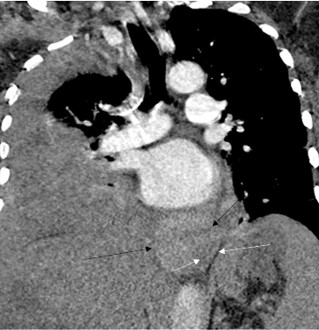

On hospital day ten, she developed acute dyspnea and hypoxia requiring supplemental O2. The hemoglobin was 6.2 g/ dL, declined from 8.6 g/dL 24 hours earlier. The patient had no hematemesis, melena, or hematochezia. CT pulmonary angiogram demonstrated a large right pleural effusion (Figure 2) and a new 9.5 × 3.6 × 5.0 cm large heterogeneous hyperdense lesion in the lower posterior mediastinum abutting the esophagus consistent with a mediastinal hematoma. No pneumomediastinum was seen to indicate an esophageal rupture. Diagnostic thoracentesis confirmed hemothorax with return of frank blood. The patient was subsequently intubated and transferred to the intensive care unit, where she was placed on vasopressors and initiated on massive transfusion protocol for hemorrhagic shock. No bloody output was noted from her orogastric tube or her rectum. Repeat CT angiogram six hours later revealed interval enlargement in the mediastinal hematoma to 10 × 7.4 × 3.8 cm and dependent higher density fluid suggesting blood in the right pleural effusion. Extensive posterior mediastinal paraesophageal varices were demonstrated but no active extravasation was noted.

Figure 2: CTA chest on hospital day 10: Coronal images showing new hyperdense paraesophageal mass consistent with hematoma (black arrows). Esophagus marked with white arrows. Also seen is new large pleural effusion.